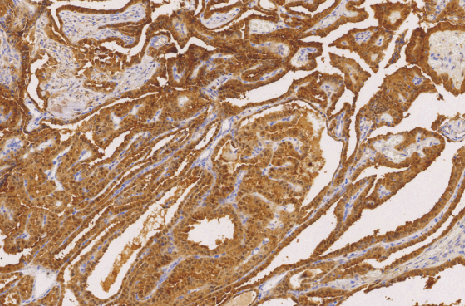

Galectin-3(Gal-3)鼠抗人半乳凝集素-3单克隆抗体

Galectin-3是分子量为30KD的半乳糖结合凝聚素家族蛋白中的-种。主要表达在细胞核、细胞质、线粒体、细胞表面和细胞外间质当中。主要作为甲状腺滤泡性腺瘤、滤泡性癌和乳头状癌的鉴别诊断。同时,根据其在微小浸润性滤泡癌的舌状浸润性强阳表达,指导对于滤泡性腺瘤和微小浸润性癌的鉴定。

- 阳性部位:胞膜,胞质,胞核

- 适用组织:石蜡切片

- 预处理:热修复